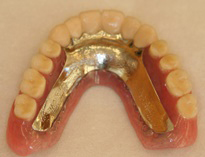

●金属床の総義歯(自費)

プラスチック系の材料とコバルトクロームやチタン等の金属からできている入れ歯です。

フレームの部分が金属なので非常に薄く仕上げることができ、使用していて違和感が少なく発音もしやすい。食べ物の温かさや冷たさに対する感覚も自然に近い。精密にできているので吸着(顎への吸い付き)がよく、外れにくい。壊れにくく長持ちである。治療費に関して選定療養費制度を利用できます。